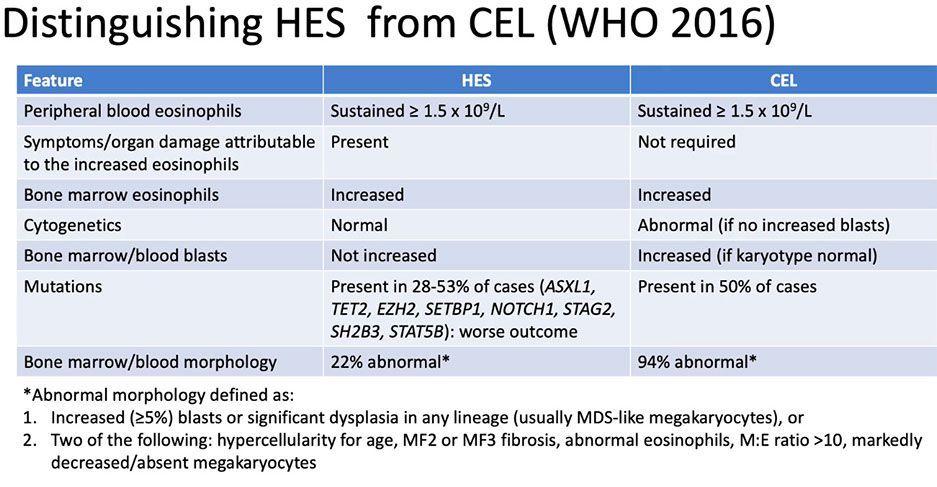

Distinguishing HES from CEL (WHO 2016)

Chronic Eosinophilic Leukemia (CEL) - not otherwise specified

_____________________________________

- Autonomous, clonal proliferation of eosinophilic precursors in PB, BM, and peripheral tissues

- Analogous to CML or CNL

- Eosinophilia (>1.5x109/L) in PB

and...

(- Blasts increased in PB (2%-19%) and/or in BM (5%-19%)

or

Clonal abnormality

- Cytogenetic: +8, iso(17q)

- Molecular genetic: JAK2 occasionally

- Excluding BCR/ABL1, and rearrangements of PDGFRA, PDGFRB, and FGFR1 )

Diagnostic criteria:

1. Eosinophilia (eosinophil count > 1.5 x 109/L)

2. WHO criteria for BCR-ABL1 positive chronic myeloid leukemia, polycythemia vera, essential thrombocythemia, primary myelofibrosis, chronic neutrophilic leukemia, chronic myelomonocytic leukemia and BCR-ABL1 negative atypical chronic myeloid leukemia are not met

3. No rearrangement of PDGFRA, PDGFRB or FGFR1, and no PCM1-JAK2, ETV6-JAK2, or BCR-JAK2 fusion

4. Blast cells constitute <20% of the cells in the peripheral blood and bone marrow, and inv(16)(p13.1q22), t(16;16)(p13.1;q22), t(8;21)(q22;q22.1), and other diagnostic features of acute myeloid leukemia are absent

5. There is a clonal cytogenetic or molecular genetic abnormality“ OR blasts account for >2% of cells in the peripheral blood or > 5% in the bone marrow

HyperEosinophilic Syndrome (HES) is persistent eosinophilia for 6 months w/o organ damage or evidence of eosinophilic clonality

- Hypereosinophilic Syndrome (HES; Persistent eosinophilia; Blasts not increased in PB or BM; No evidence of clonality);